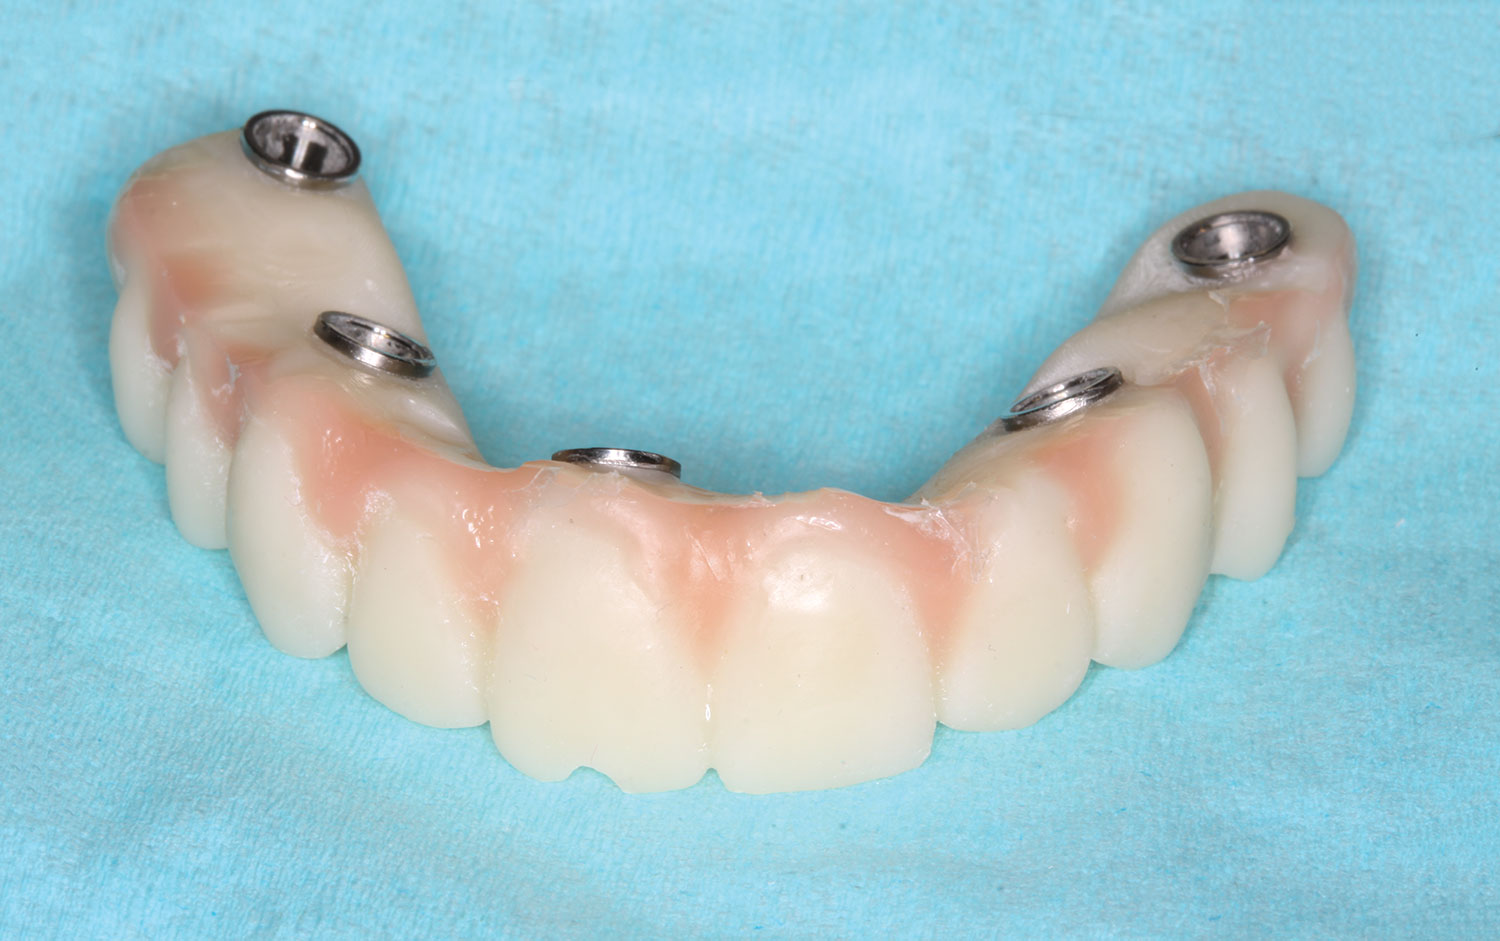

The implant company then returned an STL design file electronically via email. The office staff sent this file to the practice's 3D printer, and the appropriate color nanoceramic resin was used to print the prosthesis at 100 microns. Next, metal titanium (ti)-base cylinders, made specifically for the multi-unit abutments, were inserted into the prosthesis, which was then stained and glazed, and gingival color was applied to establish optimum esthetics (Figure 5).

Several hours later the dental team received the STL file, from which they would print the maxillary prosthesis on a 3D printer using appropriately colored nanoceramic resin. The prosthesis was stained and glazed, and metal cylinders were inserted into the undersurfaces

of the screw-access holes, each of which was specifically located to fit on the multi-unit abutments (Figure 16 and Figure 17).

Fig 5. Maxillary provisional prosthesis printed and ti-bases inserted.

Figure 5

Fig 16. Maxillary provisional prosthesis printed and ti-bases inserted.

Figure 16

Fig 17. Maxillary provisional prosthesis with screw-access holes in prosthetically correct locations.

Figure 17